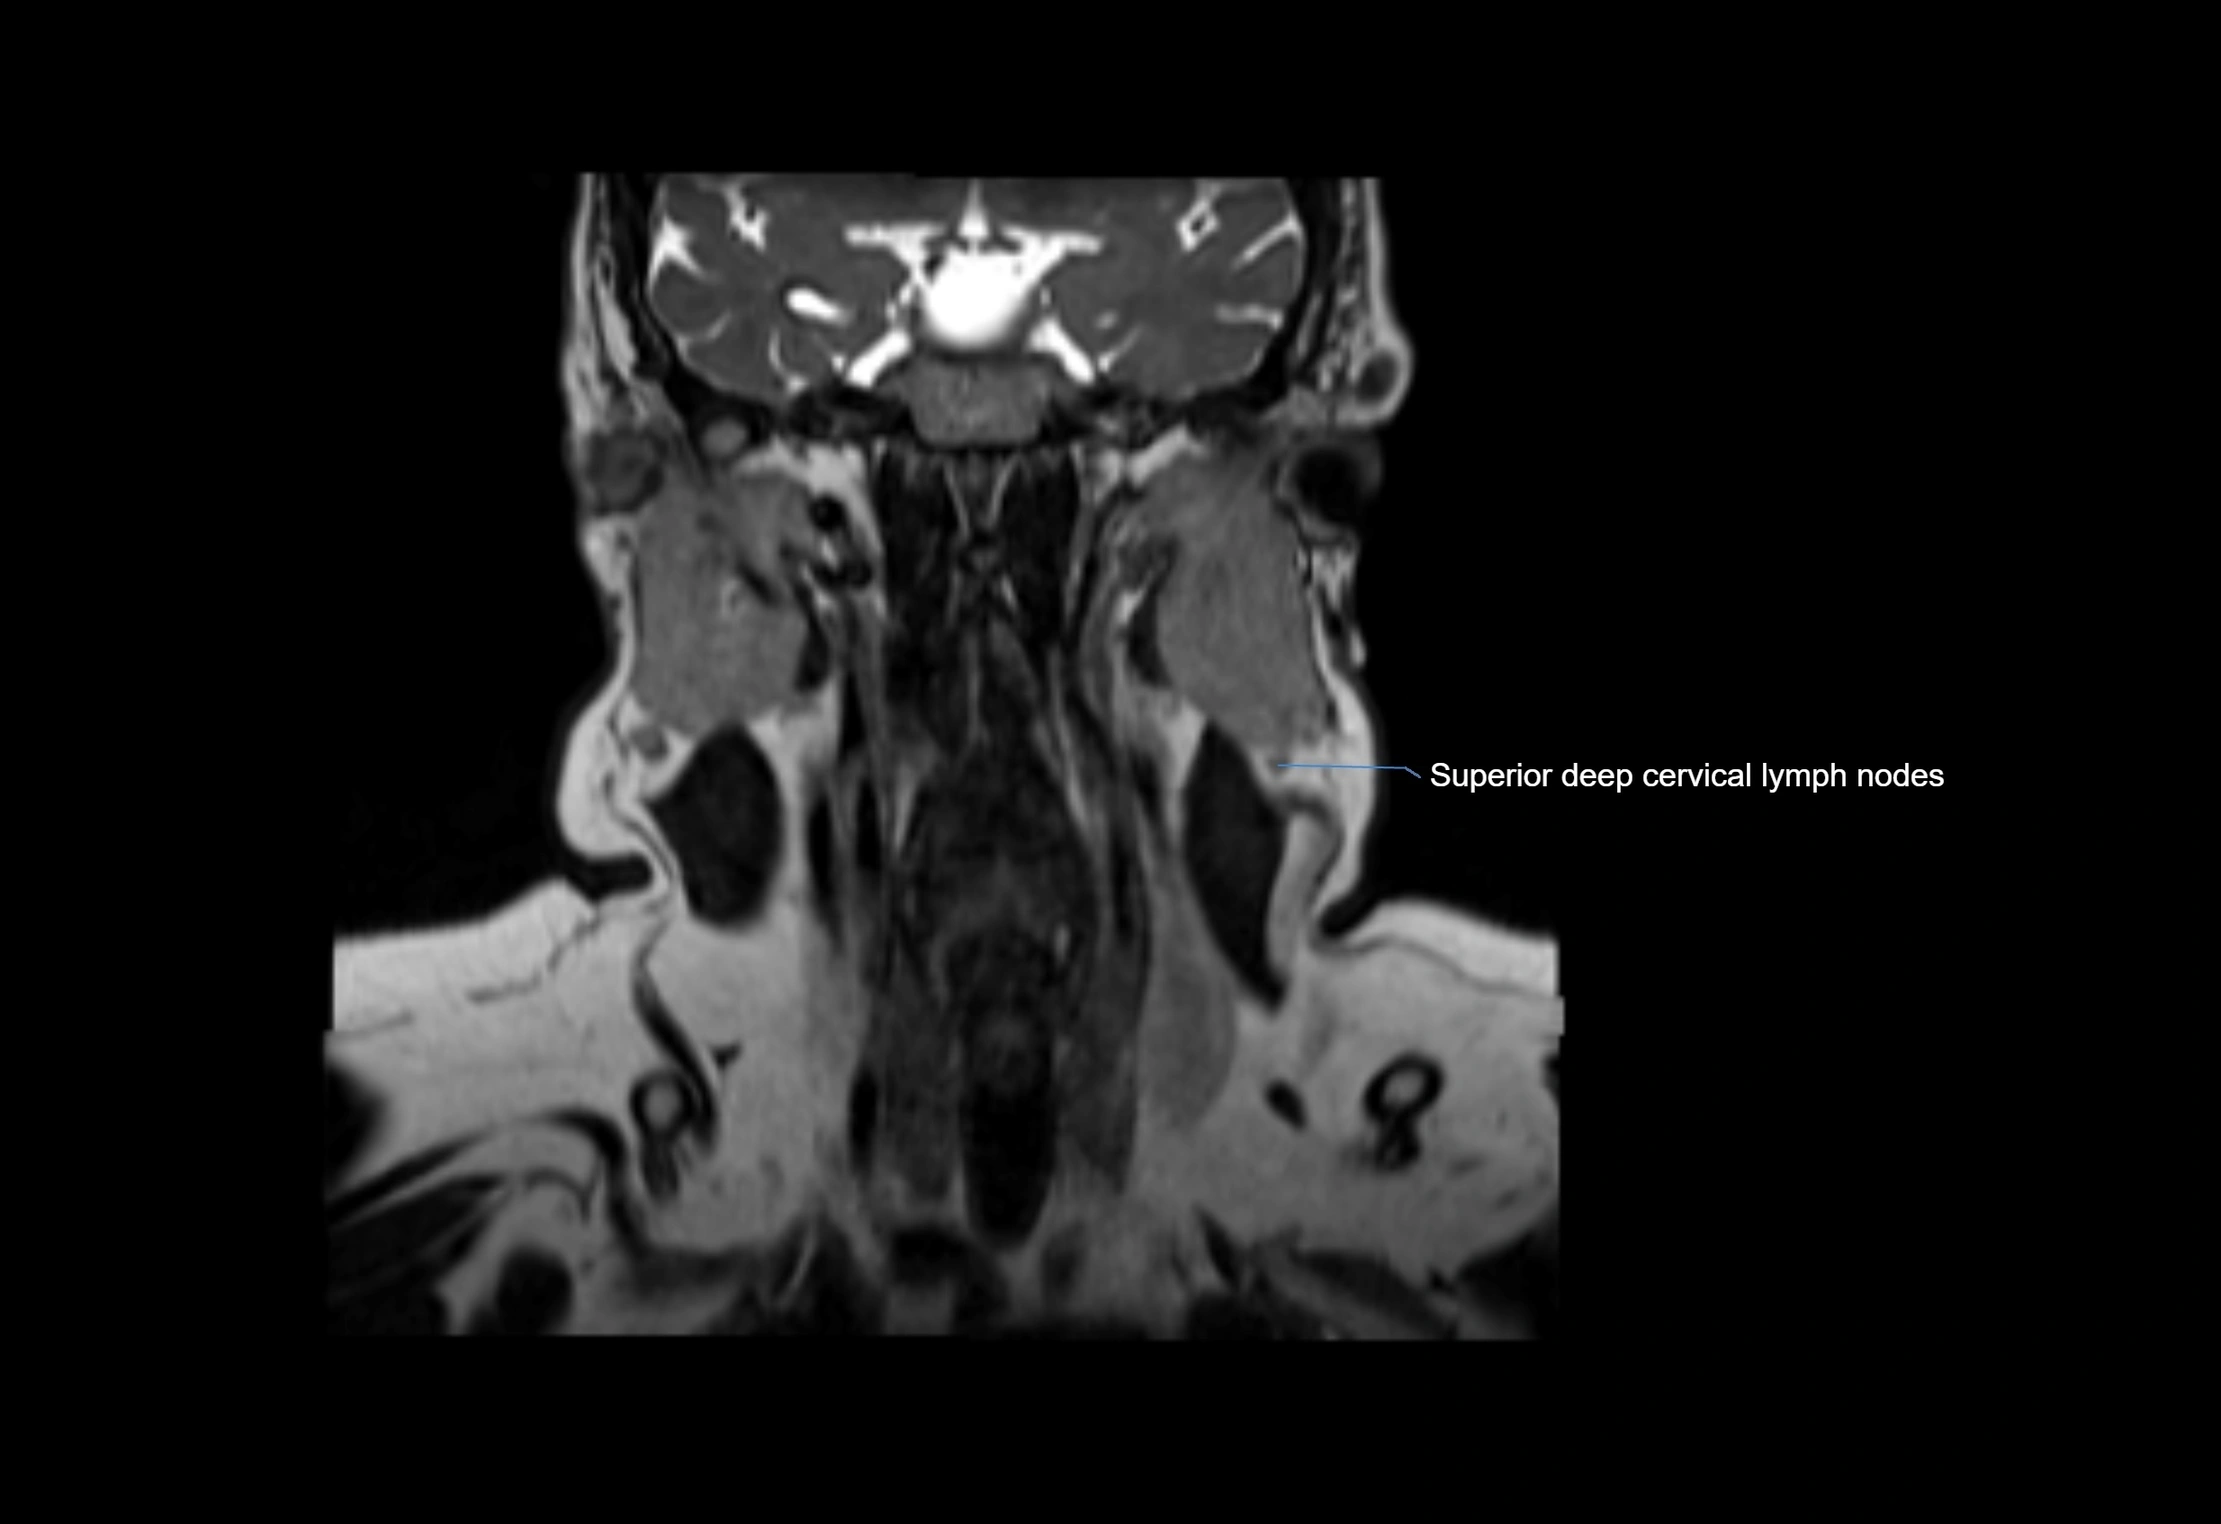

Accessory lymph nodes are small, secondary lymph nodes located along the main facial and cervical lymphatic chains, often adjacent to primary lymph nodes, such as preauricular, submandibular, or occipital nodes. They are typically less than 5 mm in diameter, embedded within subcutaneous fat or connective tissue, and may be variable in number and location. These nodes provide additional filtration and immune surveillance for lymph collected from the face, scalp, and neck regions. Accessory lymph nodes are usually non-palpable in healthy individuals but may enlarge in response to infection, inflammation, or metastasis, making them clinically significant.

• Found along primary lymph node chains, including preauricular, submandibular, parotid, and occipital regions

MRI Appearance

T1-weighted images:

• Normal accessory nodes appear as small, oval hypointense to intermediate signal structures within subcutaneous fat

• Surrounded by hyperintense fat, enhancing contrast for visualization

• Pathological nodes may appear enlarged or rounded, sometimes with cortical thickening

T2-weighted images:

• Nodes show intermediate signal, with surrounding fat bright

• Useful for detecting edema, inflammation, or infiltration

• Fatty hilum may appear slightly hyperintense relative to cortex